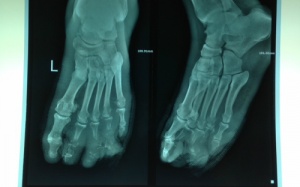

Bệnh đái tháo đường là nguyên nhân gây ra 1,5 triệu ca tử vong trên thế giới trong năm 2015, theo WHO. Bên cạnh các biến chứng tại tim, hệ thần kinh, võng mạc, thận…, bệnh đái tháo...

Tổn thương thần kinh do bệnh đái tháo đường là dạng tổn thương thường gặp khiến cho bệnh nhân bị đau đớn, lở loét tay chân, dẫn đến đoạn chi, thậm chí là tử vong.